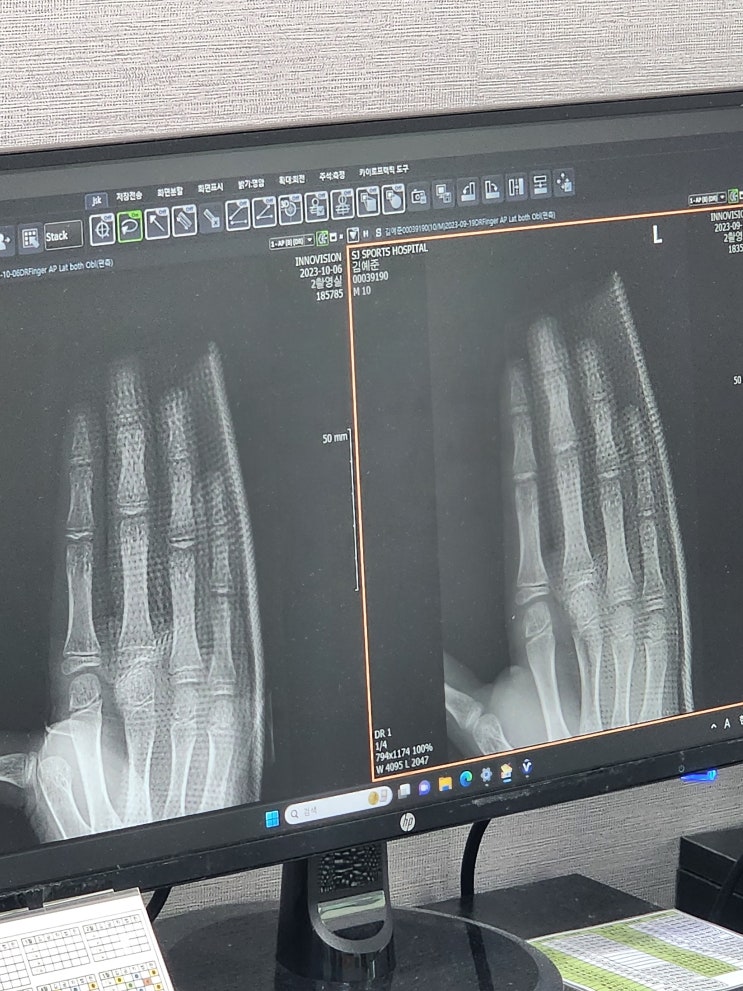

야구선수 손가락 골절 전문 정형외과 후기

돌아보면 야구를 그만둬야하나 순간이 많았지만 가장 무겁게 다가왔던 것은 부상이었다. 운동을 하다보면 ...